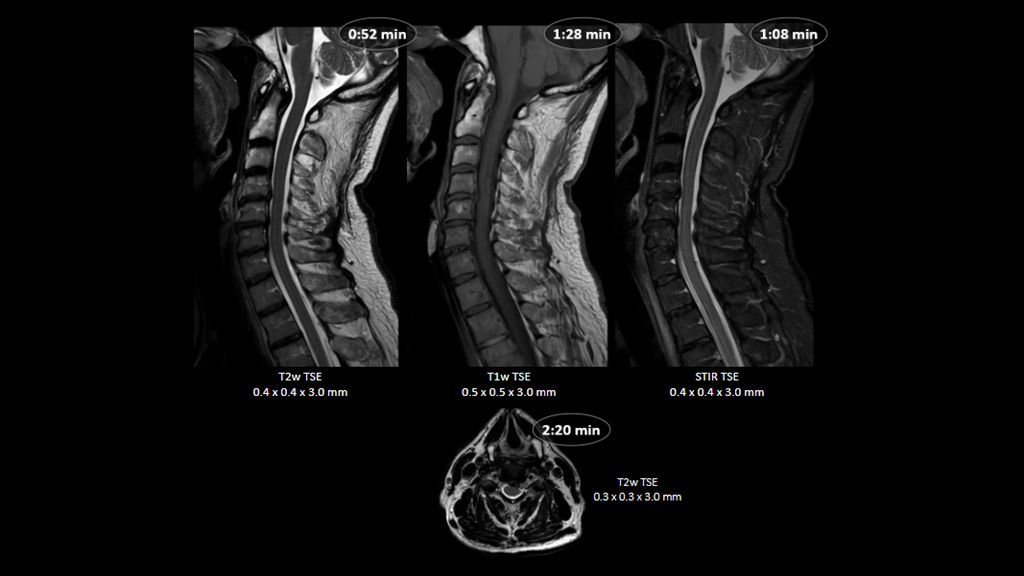

1. Compared to SENSE imaging, with no loss in image quality.

2. Reconstruction technology Compared to conventional (SENSE/ Compressed SENSE, SmartSpeed AI) imaging. Sharpness was evaluated with phantom scanning.

3. dStream based systems, not available for Prodiva and Multiva systems.